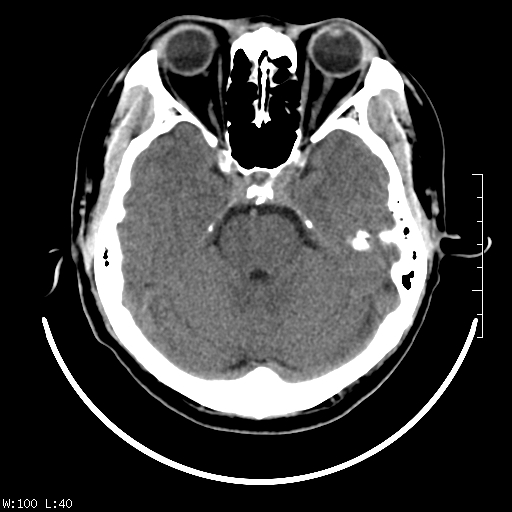

标题: CT22236:男,45,经常头痛。看看脑干正常吗? [打印本页]

标题: CT22236:男,45,经常头痛。看看脑干正常吗?

未见明显异常,建议ct增强或mri检查。

没见异常密度及形态改变啊,我认为是正常的。

颅脑ct轴位平扫颅内未见明确异常。

颅脑ct平扫未见明确异常,必要时mri检查。

颅脑ct平扫未见异常